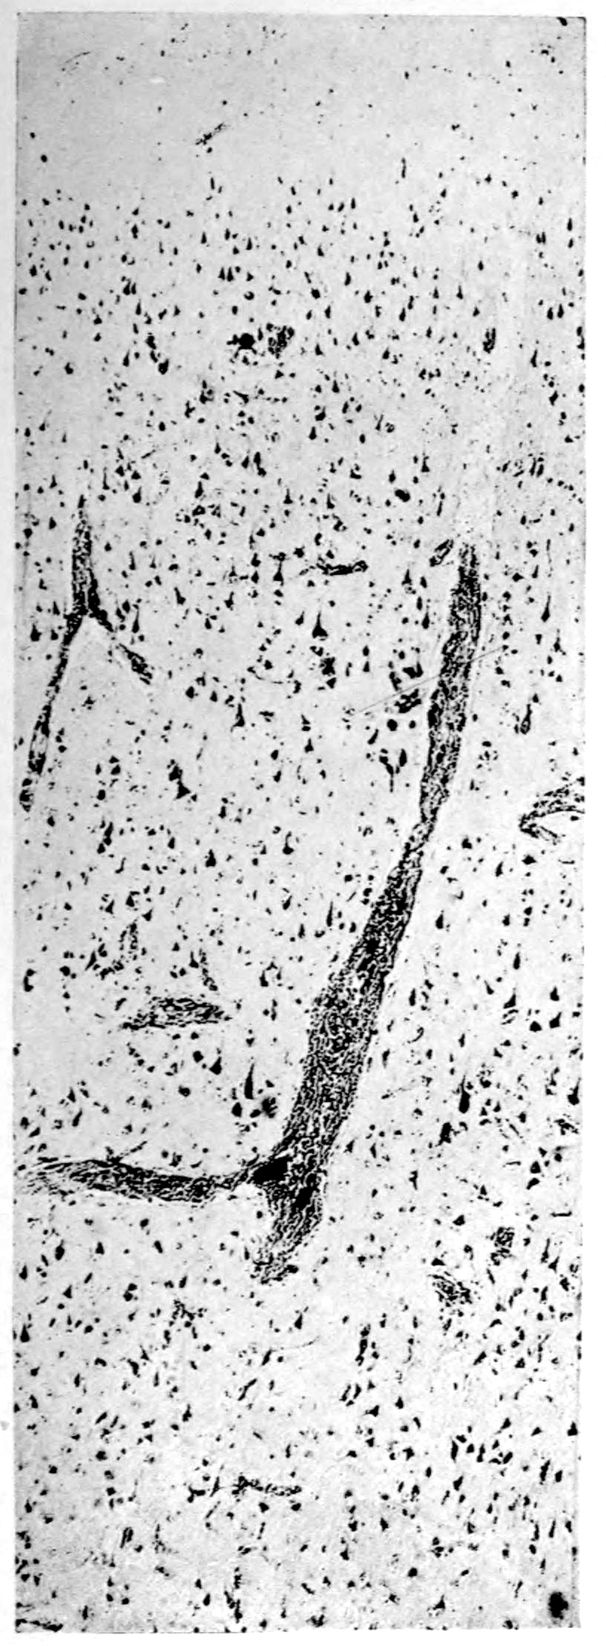

Case I. Spinal Cord (Three Levels) Showing:

A. Marginal sclerosis—effect of old meningitis now extinct.

B. Posterior column sclerosis—effect of meningitis about posterior roots also now extinct.

C. Bilateral pyramidal tract sclerosis—effect of cerebral thrombotic lesions.

Note distortion of tissues in B and C, partly artificial (tissues in places diffluent).

Vascular neurosyphilis—effects of syphilitic thrombosis of Sylvian artery 10 years before death. (Case 4.)

Case 4. (See previous figure for brain lesion.) Three levels of the spinal cord showing unilateral pyramidal tract sclerosis, 10 years after cerebral thrombosis.